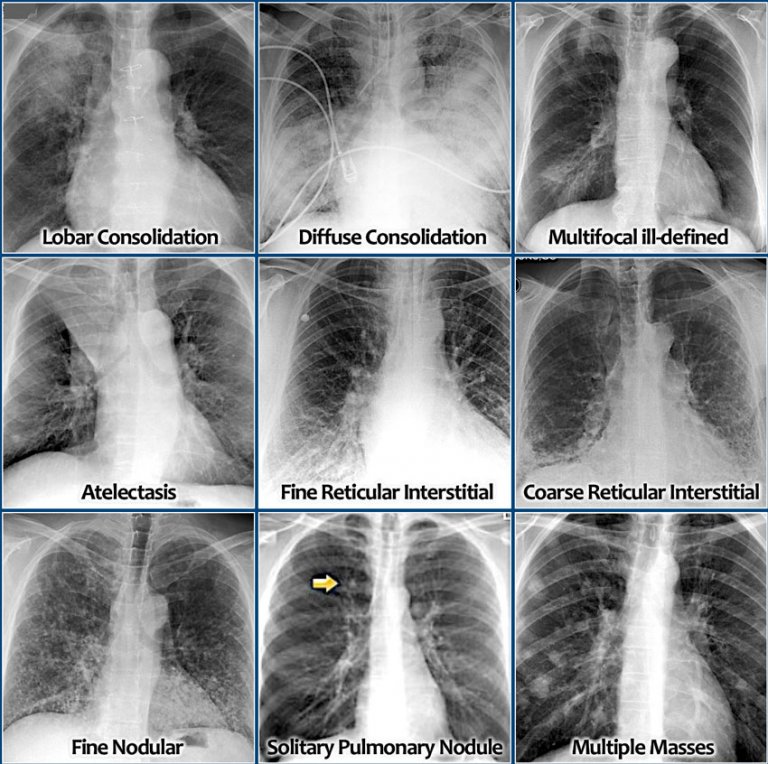

From radiologyassistant.nl

The Radiology Assistant Chest XRay Lung disease How Do You Know If You Have A Fungal Lung Infection Fungal lung infections are a group of respiratory conditions caused by various types of fungi. Common symptoms include coughing, wheezing, shortness of breath, chest pain, fatigue, and fever. Common symptoms include persistent cough, shortness of breath, chest pain, fever, fatigue, and weight loss. It happens when the spores mix with the air and are inhaled, or when an inactive infection. How Do You Know If You Have A Fungal Lung Infection.